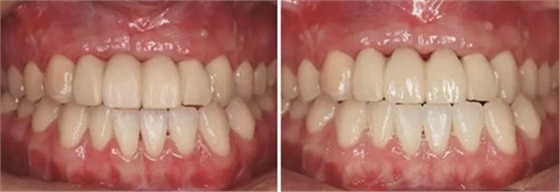

圖17 CBCT測(cè)量骨量變化 圖18 早期修復(fù)戴牙當(dāng)天

圖19 早期修復(fù)1月 圖20 早期修復(fù)2月

圖21 早期修復(fù)3月 圖22 早期修復(fù)3月打開三角間隙

圖23 早期修復(fù)4月 圖24 早期修復(fù)7月切除軟組織增生后

圖25 早期修復(fù)7月調(diào)改橋體部形態(tài)為卵圓形并高度拋光 圖26 早期修復(fù)8月

圖27 早期修復(fù)8月調(diào)改后 圖28 早期修復(fù)10月